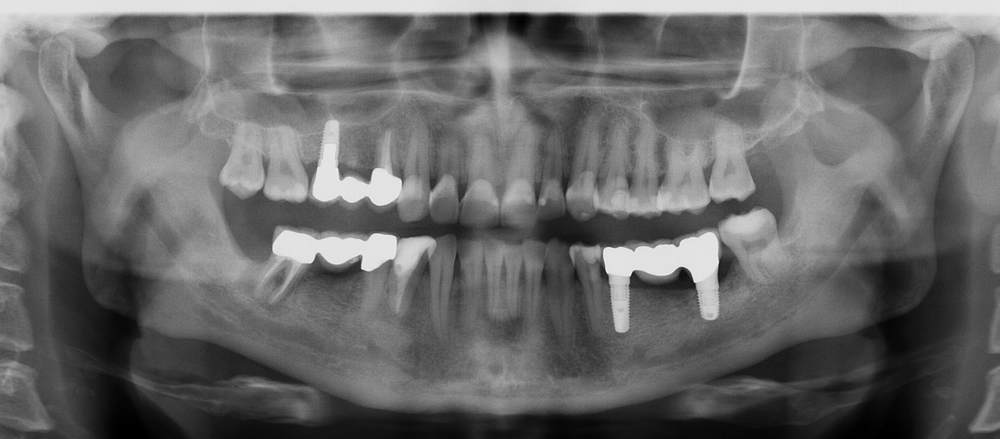

Hier ein Beispiel aus der Praxis: